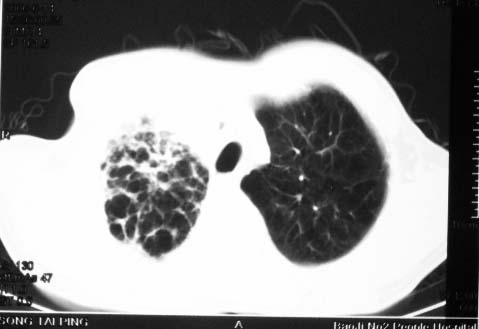

影象表现:右肺上叶大片状、网格状及索条致密影,蜂窝影,其内参杂斑点状小结节,密度不均匀,内见含气支气管像,纵隔内见肿大淋巴结.

影象表现:右肺上叶大片状、网格状及索条致密影,蜂窝影,其内参杂斑点状小结节,密度不均匀,内见枯枝样含气支气管像,纵隔内见肿大淋巴结.胸膜广泛增厚,前胸壁似受累.少量胸腔积液.纵隔内淋巴结的直径>1.5cm.右侧胸廓体积缩小.考虑:1 肺结核合并间质纤维化 2 细支气管肺泡癌

右肺上叶大片状、网格状及索条致密影,蜂窝影,其内参杂斑点状小结节,密度不均匀,内见枯枝样含气支气管像,纵隔内见肿大淋巴结.胸膜广泛增厚,前胸壁受累增厚.少量胸腔积液.纵隔内淋巴结的直径>1.5cm.右侧胸廓体积缩小.考虑: 细支气管肺泡癌并肺内癌性淋巴管炎。